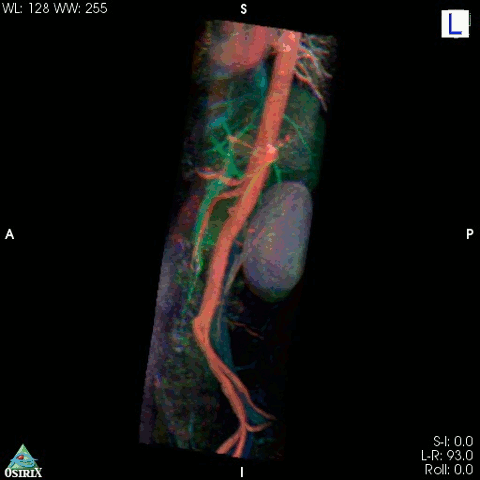

5. Розфарбована МРТ аорти